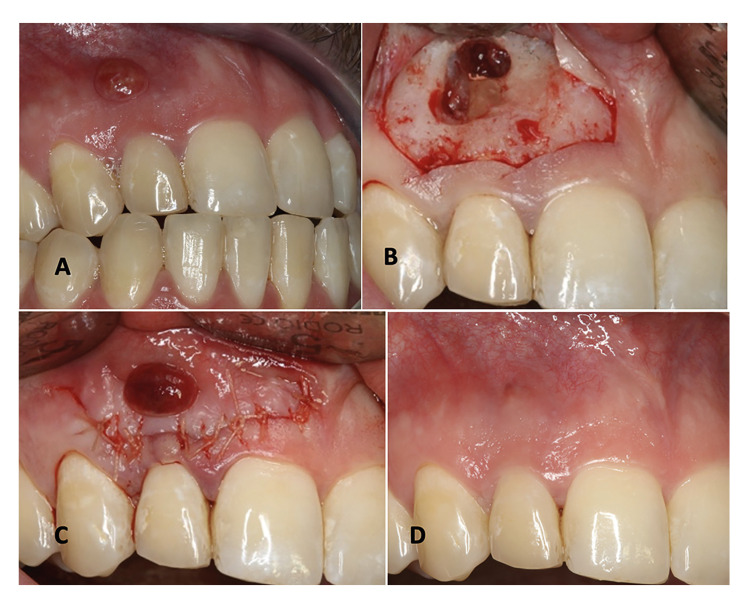

Background: A study was made of the clinical periodontal changes and buccal cortical bone modifications using cone-beam computed tomography (CBCT) in anterior maxillary teeth with chronic apical periodontitis one year after periapical surgery with submarginal incision.

Material and methods: A prospective case series analysis was made of anterior teeth subjected to apical surgery and submarginal incision with a follow-up period of 12 months. Clinical periodontal parameters were recorded, along with tomographic measurements of the buccal cortical bone and volume of the lesion (in mm3) before and one year after surgery. Success was assessed based on the clinical and tomographic data.